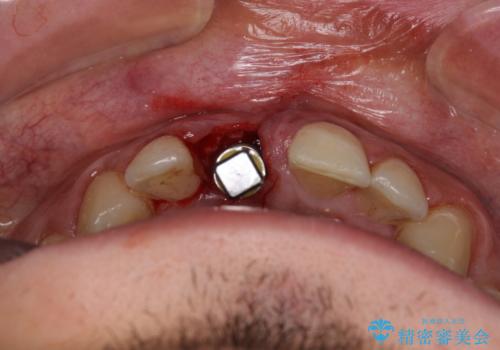

磨き残しなどによるプラークの付着が多いため、仮歯の用意と手術アポイントの調整を行っている間に口腔内のクリーニングなどを施し、環境がある程度改善されたのちに、抜歯即時インプラント埋入、即時荷重(インプラント埋入時に仮歯の装着)の予定で治療を行うこととしました。

日本語でのコミュニケーションが非常に困難な状態から治療が始まりましたが、通訳にお越しいただいた同僚の方や、ご本人の日本語コミュニケーション力の上昇により、無事に治療を終えることができました。

そのため、現在の位置よりも歯と歯肉の位置が退縮する方向に移動する可能性があり、前歯2本の歯肉位置が大きくずれることとなるため、本人との相談のうえ、天然歯が萌えているような歯肉状態とはならないものの、2本の段差が少ない状態にて治療を終えることとなりました。